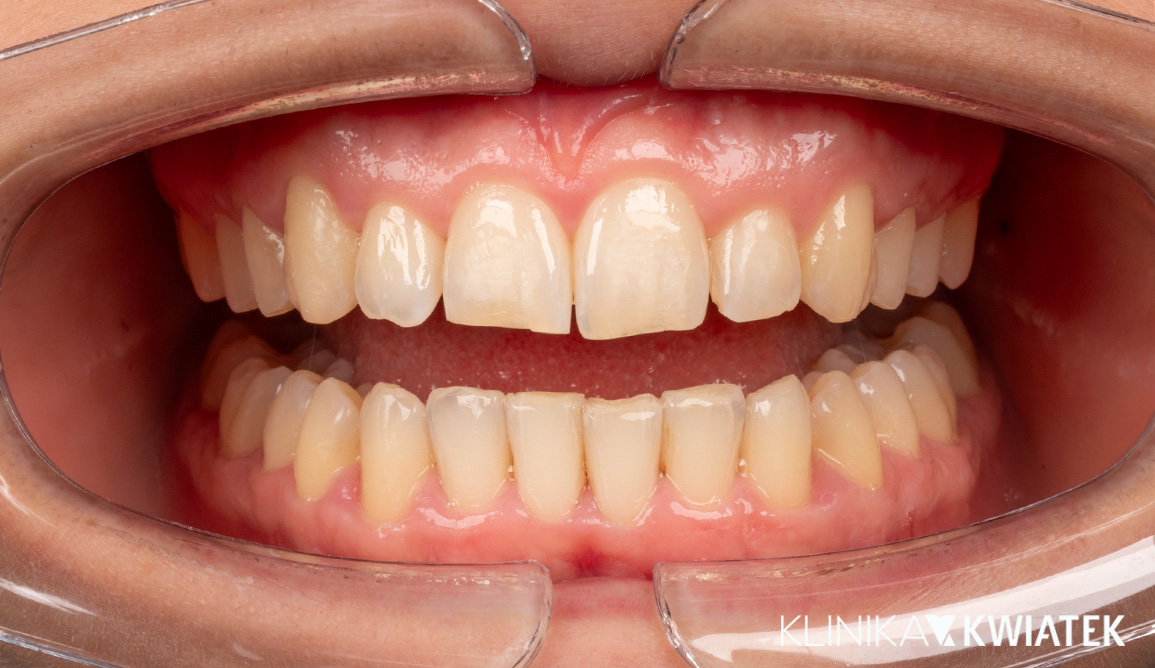

Olśniewająca metamorfoza uśmiechu – gdy estetyka łączy się ze zdrowiem!!

Pacjentka zgłosiła się do naszej kliniki z problemami związanymi z licznymi ubytkami, startymi zębami, krwawieniem dziąseł oraz nieestetycznymi wypełnieniami. Po wykonaniu pełnej diagnostyki przygotowaliśmy indywidualny plan leczenia obejmujący profesjonalną higienizację, wymianę wypełnień, leczenie kanałowe, wybielanie, ekstrakcje i augmentację kości, a następnie wszczepienie implantów MIS C1. Finalnym etapem była odbudowa protetyczna przy użyciu pełnoceramicznych koron CAD/CAM, idealnie dopasowanych do koloru i kształtu naturalnych zębów. Efekt to zdrowa jama ustna, przywrócona funkcja żucia i estetyczny, harmonijny uśmiech, który odmienił komfort życia Pacjentki.